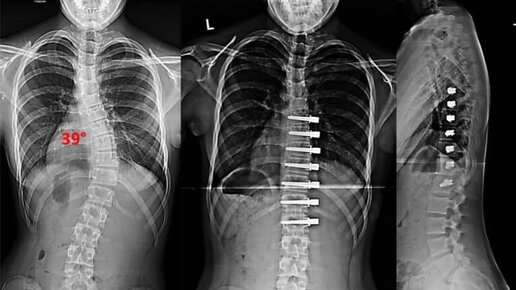

В ПНИПУ научили искусственный интеллект диагностировать сколиоз

Более 40 процентов населения планеты страдает сколиозом. Он приводит к серьезным последствиям для здоровья. Диагностика заболевания обычным врачебным осмотром или лучевыми методами не всегда эффективна и безопасна. Ученые Пермского Политеха создали и обучили нейросеть находить ключевые точки спины при диагностике сколиоза. Применение компьютерного зрения сделает определение заболевания более точным и доступным для пациента. Статья с результатами исследования опубликована в журнале «Вестник ПНИПУ...